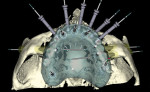

Ten radiopaque markers (gutta percha, Hygenic®, Coltène/Whaledent Group, www.coltene.com) were placed in the maxillary complete denture to prepare the denture for a specific guided- surgery protocol (NobelClinician™ Software, Nobel Biocare USA, LLC, www.nobelbiocare.com).23-30 This protocol uses a dual cone beam computed tomography (CBCT) scan procedure. The first CBCT scan (i-CAT®, Imaging Sciences International Inc., www.imagingsciences.com) was taken with the patient’s dentures in place, and a second CBCT scan was taken of the maxillary complete denture alone. The two scans were exported in Digital Imaging and Communications in Medicine (DICOM) format and loaded into the guided-surgery software, where a 3-dimensional (3-D) virtual working model of the patient was generated (Figure 4 through Figure 7) to enable virtual implant planning to be performed. Because the patient’s denture contained the approved esthetic arrangement of the teeth, the implants could be placed virtually in the most prosthetically favorable position.

The finalized virtual implant plan (Figure 8 through Figure 12) consisted of two 10-mm implants and one 13-mm implant in the maxillary anterior region, which engaged the cortical bone at the inferior border of the nasal cavity. The plan called for two 18-mm implants to be placed in the pterygomaxillary31,32 region at an approximately 45-degree angle to the occlusal plane. These pterygomaxillary implants would provide posterior support for the restoration and eliminate a posterior cantilever.33-36 In order to shorten the span between the three anterior and two posterior implants, three zygoma implants were planned on the pre-surgica lcomputer model to transect through the sinus cavity and engage the zygoma bone. All implants in the virtual planning were external-connection regular-platform implants (Brånemark® System, Nobel Biocare).

Once the zygoma implants were positioned virtually, the sizes of each zygoma implant were recorded and screenshots of the planning were taken. The virtual zygoma implants were then switched to standard-length implants in the exact same axis (Figure 13). The appropriate surgical template sleeve accompanied the standard-length implants, which could be incorporated into the surgical template. While these standard Brånemark sleeves would not permit actual zygomatic implant placement, they would enable the surgeon to create a starting point for the access of the zygoma position into the alveolar bone. This provided the ability to put the coronal aspect of the zygoma implant in the best prosthetic position, which is a tremendous advantage for laboratory construction of the final prosthesis. It also gives the surgeon an opportunity to study the 3-D anatomy of the patient prior to the surgery.